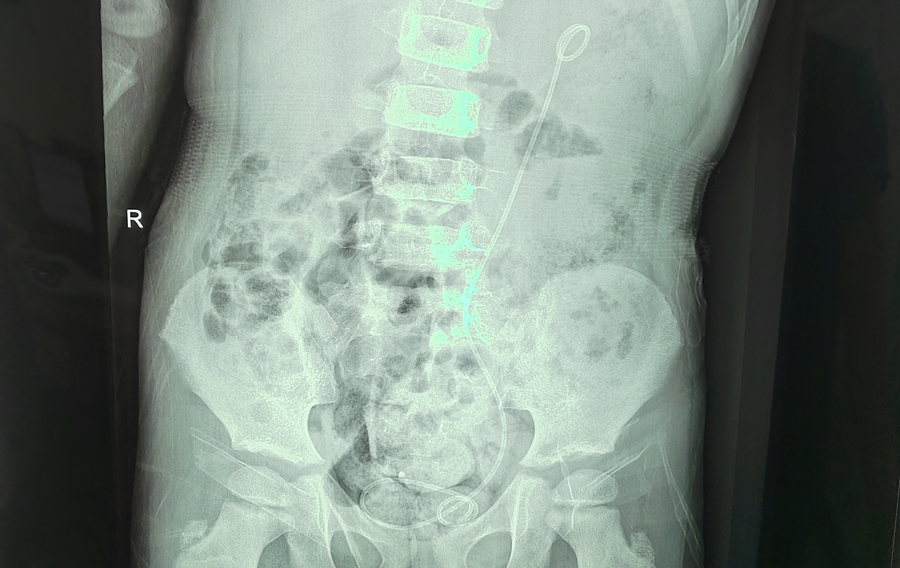

吻合成功,左侧输尿管通畅

接下来是将剪断的输尿管进行吻合。由于切除了长息肉段的输尿管,此时再把存留的输尿管上下断端进行吻合,张力极大。能否吻合成功也是手术的关键。此时,手术室内静悄悄的,所有人的注意力都集中在腹腔镜的显示屏上,牵引、缝合、打结、置入输尿管支架管……在整个手术团队的精细操作和默契配合下,两段输尿管终于被成功吻合。当看到留置的尿袋里出现红色尿液时,说明吻合成功,输尿管通畅,所有人悬着的心才放了下来。术后,多多恢复得非常好,8月31日顺利出院。他的腰腹疼痛、肾盂扩张、肾脏皮质变薄症状会随着康复而明显缓解,后续定期复查即可。儿医人凭借这种不懈寻求疾病真相的精神,努力守护着儿童的健康。